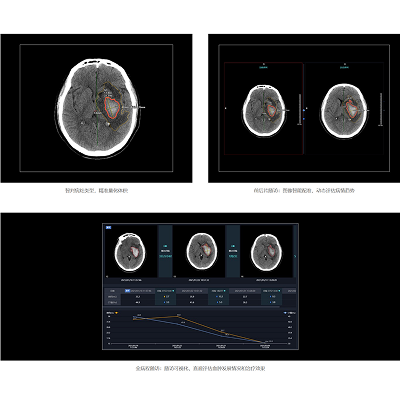

联影智能CT颅内出血智能分析与随访系统,可精准检出颅内出血、水肿、中线移位,全自动量化病灶信息并进行危急值预警,支持前后片随访和全病程随访,实现随访可视化;提供相关量表,全面辅助医生快速评估患者病情,制定诊疗方案和预后。

联影智能CT颅内出血智能分析与随访系统可快速判别卒中类型,检出颅内出血、水肿、中线移位,提供病灶量化信息,其检出急性期颅内出血患者的灵敏度为97.0%、特异度为98.7%,计算出血病灶体积的整体准确率为95.9%,同时,系统还可帮助辨别微小出血和钙化,帮助低年资医生或基层医院精准辨别,减少误诊率,为患者救治争取宝贵时间。